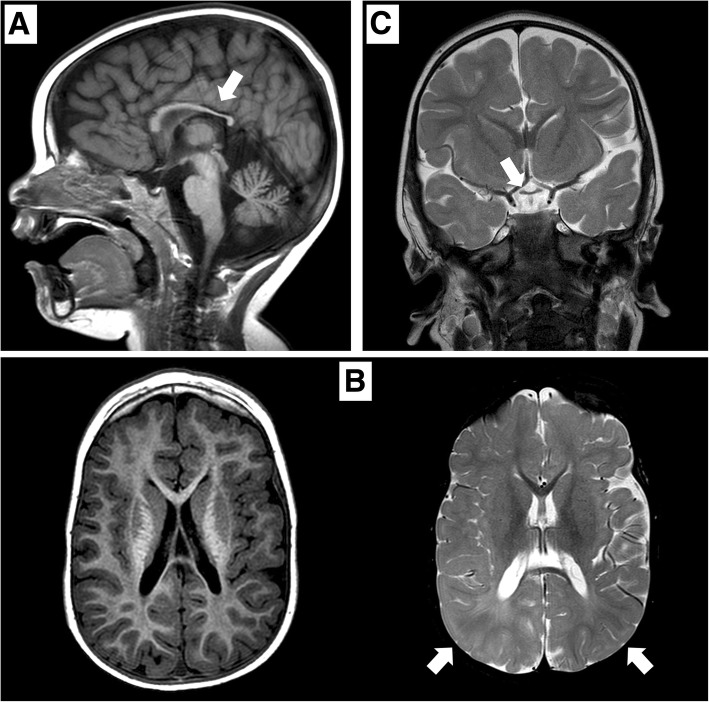

矢狀位 T1 加權(quán)圖像顯示胼胝體發(fā)育不全(白色箭頭)。 b 軸向 T1 加權(quán)(左)和軸向 T2 加權(quán)(右)圖像顯示胼胝體發(fā)育不全和雙側(cè)皮層下頂葉白質(zhì)(白色箭頭)中改變的、不明確的信號。 c 顯示視交叉發(fā)育不全的冠狀 T2 加權(quán)圖像(白色箭頭)

在 2 歲時,患者無法保持目光接觸,也沒有發(fā)展語言技能。 直到 3 歲時,他才能獨(dú)立坐下。此時,頭顱 MRI 顯示雙側(cè)視神經(jīng)發(fā)育不全,并證實(shí)胼胝體發(fā)育不全(圖 (圖 1).1)。 為評估先天性心臟缺陷而進(jìn)行的超聲心動圖顯示無阻塞的室間隔肥大。